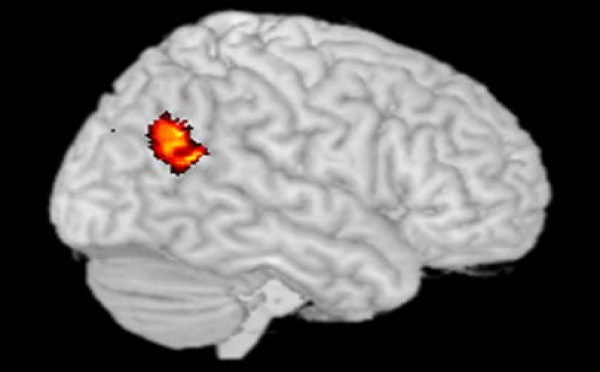

Determinan el área del cerebro que se activa cuando juzgamos a los demás - 24/05/2008

Neurocientíficos del MIT han conseguido definir, utilizando la tecnología de captación de imágenes por resonancia magnética funcional (fMRI), el área del cerebro que se activa cuando emitimos un juicio de valor moral sobre el comportamiento de otras personas. El descubrimiento implicaría que no sólo los procesos cognitivos más sencillos se reflejan en la actividad cerebral, sino que también los procesos cognitivos complejos de mayor nivel están vinculados a áreas concretas de la corteza del cerebro. En este caso, los juicios morales ponen en marcha la unión temporoparietal que es el lugar en el que se encuentran el lóbulo temporal y el lóbulo parietal del cerebro. Se sabe que esta región juega un papel fundamental en los procesos de distinción entre el yo y los demás.